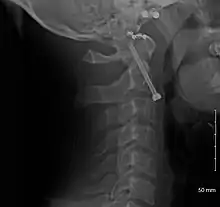

A fracture of the base of the dens as seen on plain X-ray